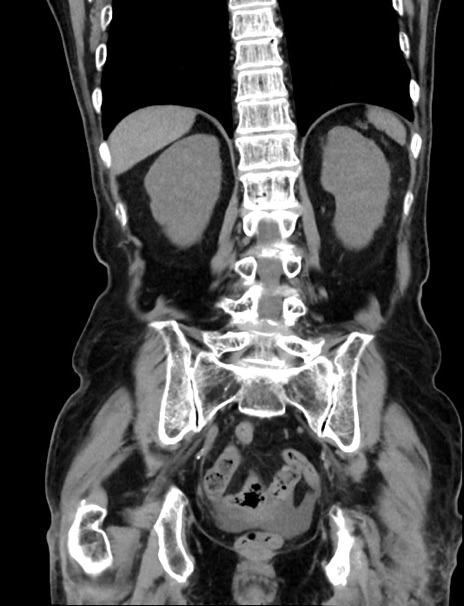

症例33(冠状断像)

【症例】70歳代 女性

【主訴】心窩部痛

【現病歴】延髄病変の精査・加療にて神経内科入院中。本日より心窩部痛あり。

【身体所見】右下腹部を中心に圧痛と反跳痛あり。

【データ】WBC 10900、CRP 0.02